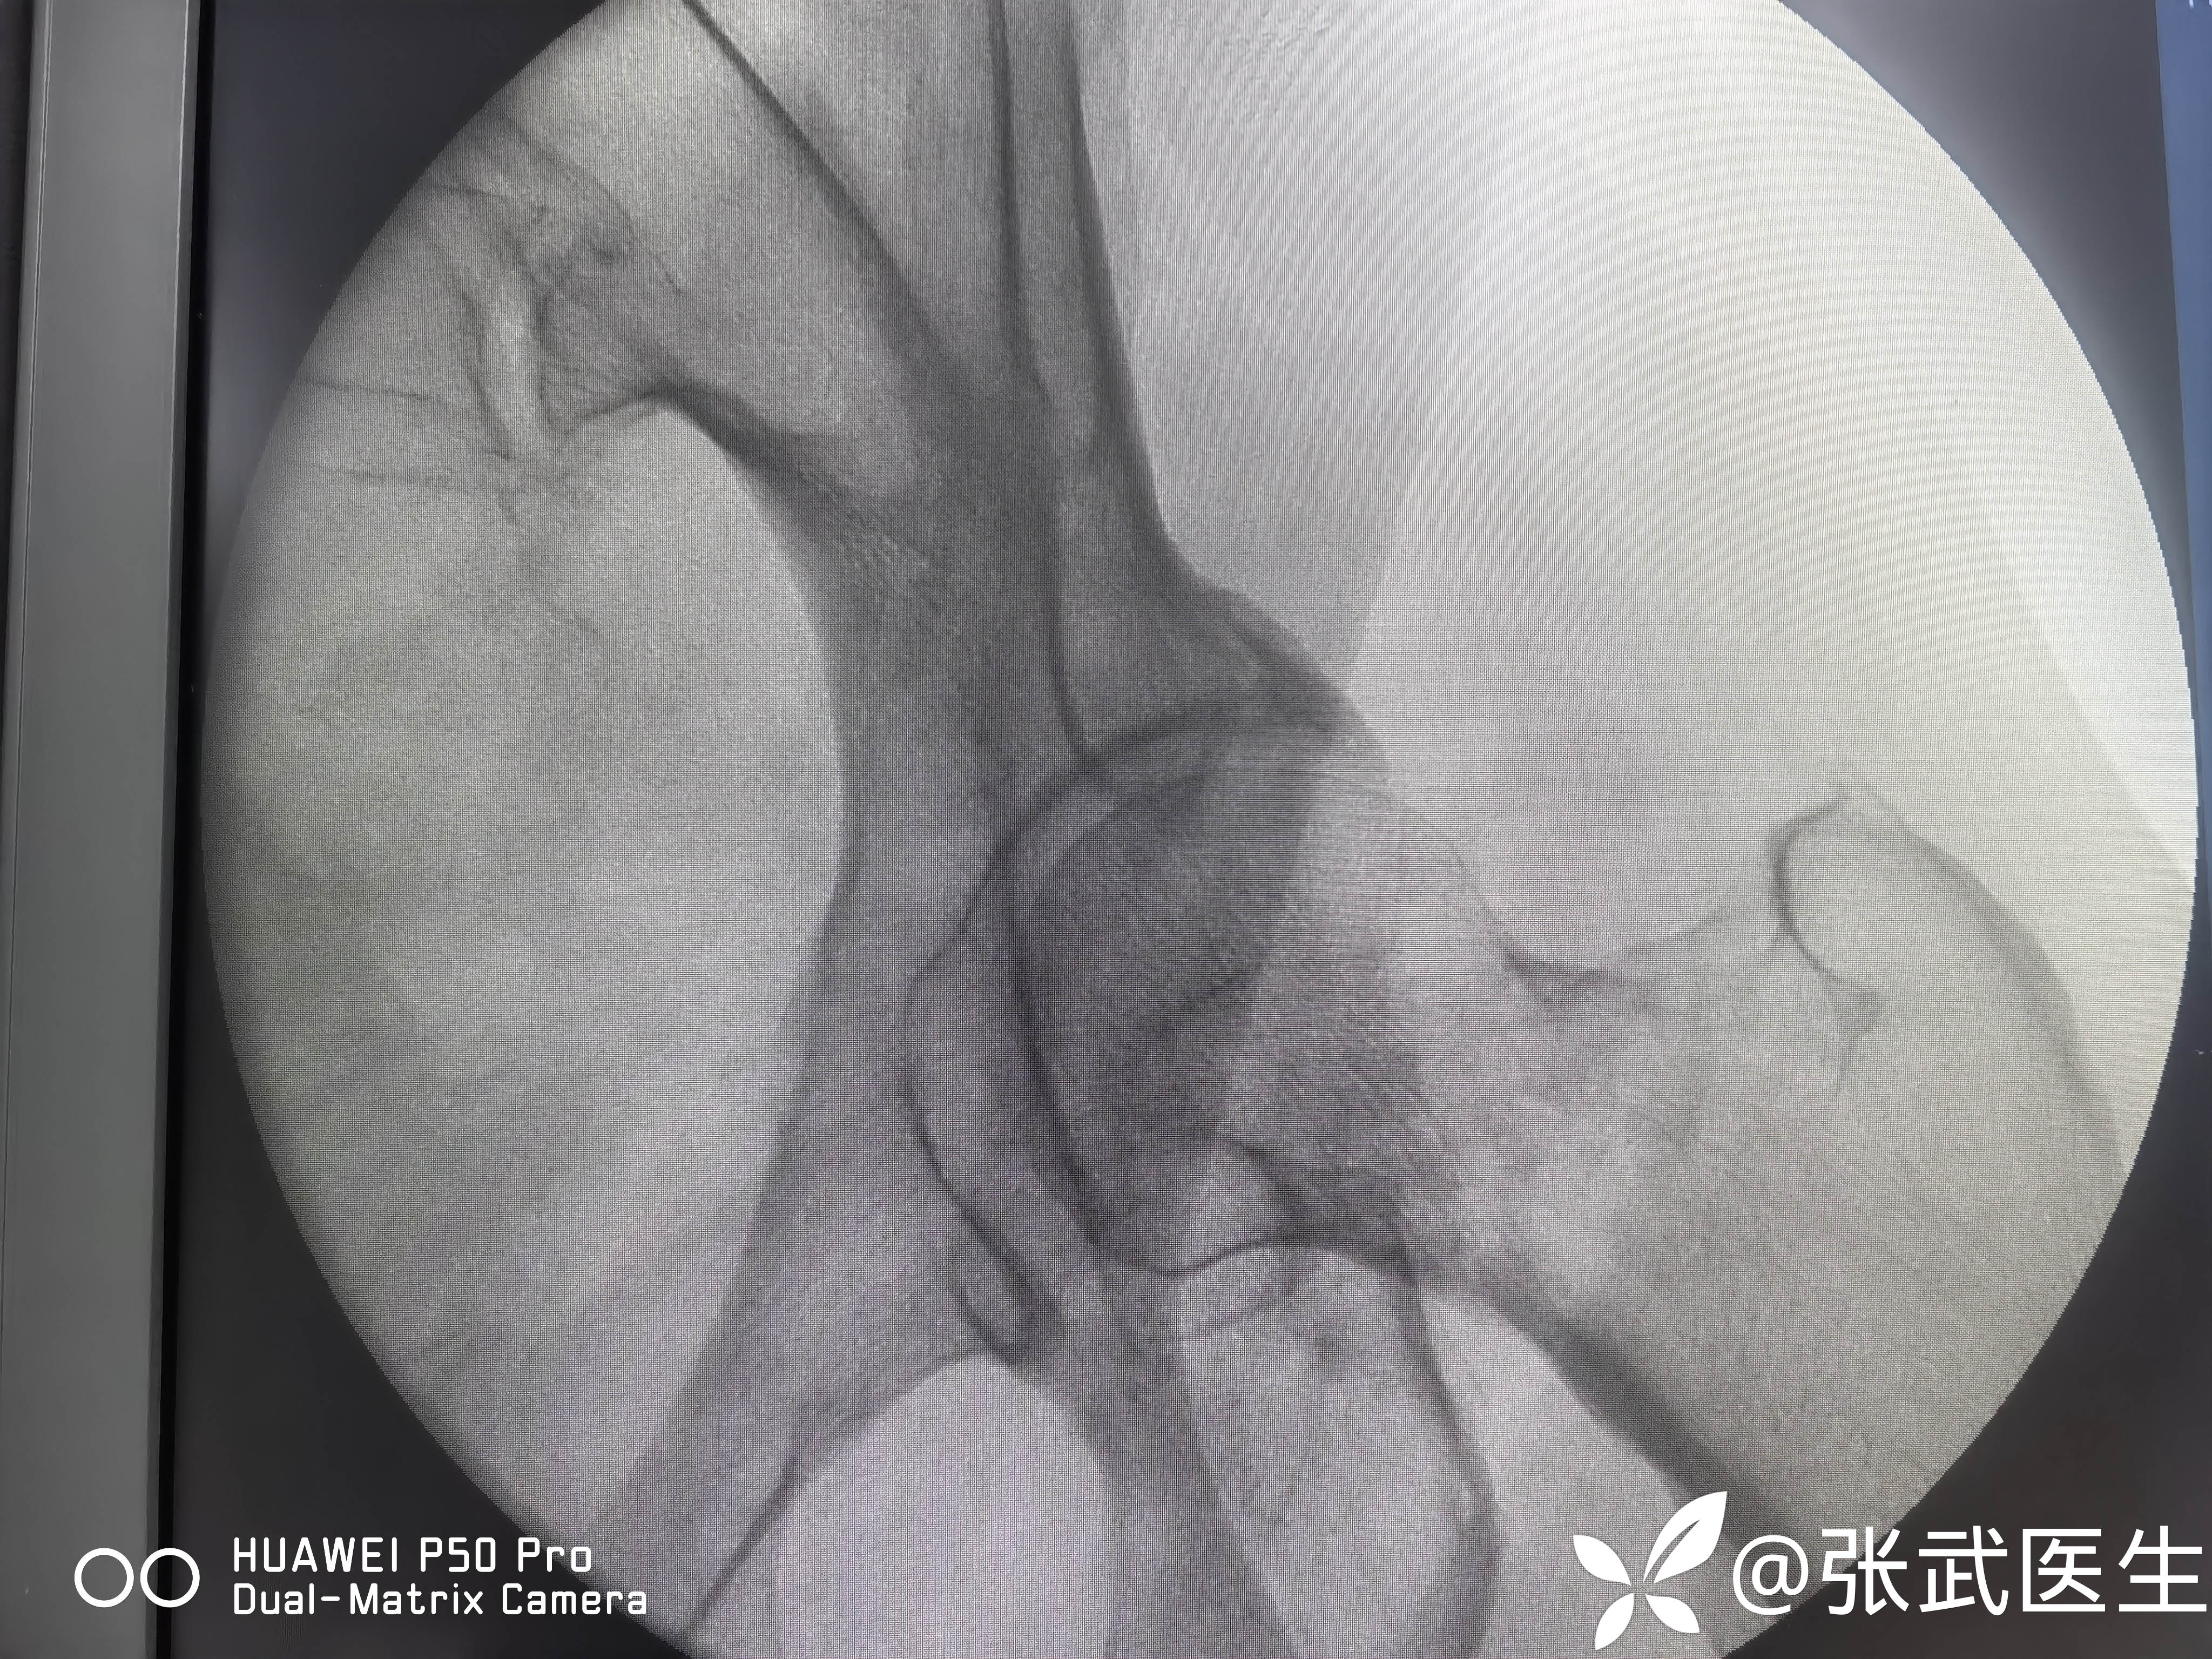

诊断:左股骨颈骨折 Garden II型

术前:

pauwels>50度

骨折复位情况